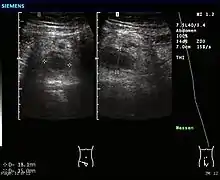

In children the clinical examination is important to determine which children with abdominal pain should receive immediate surgical consultation and which should receive diagnostic imaging.[40] Because of the health risks of exposing children to radiation, ultrasound is the preferred first choice with CT scan being a legitimate follow-up if the ultrasound is inconclusive.[41][42][43] CT scan is more accurate than ultrasound for the diagnosis of appendicitis in adults and adolescents. CT scan has a sensitivity of 94%, specificity of 95%. Ultrasonography had an overall sensitivity of 86%, a specificity of 81%.[44]

Ultrasound

Abdominal ultrasonography, preferably with doppler sonography, is useful to detect appendicitis, especially in children. Ultrasound can show the free fluid collection in the right iliac fossa, along with a visible appendix with increased blood flow when using color Doppler, and noncompressibility of the appendix, as it is essentially walled-off abscess. Other secondary sonographic signs of acute appendicitis include the presence of echogenic mesenteric fat surrounding the appendix and the acoustic shadowing of an appendicolith.[45] In some cases (approximately 5%),[46] ultrasonography of the iliac fossa does not reveal any abnormalities despite the presence of appendicitis. This false-negative finding is especially true of early appendicitis before the appendix has become significantly distended. Also, false-negative findings are more common in adults where larger amounts of fat and bowel gas make visualizing the appendix technically difficult. Despite these limitations, sonographic imaging with experienced hands can often distinguish between appendicitis and other diseases with similar symptoms. Some of these conditions include inflammation of lymph nodes near the appendix or pain originating from other pelvic organs such as the ovaries or Fallopian tubes. Ultrasounds may be either done by the radiology department or by the emergency physician.[47]